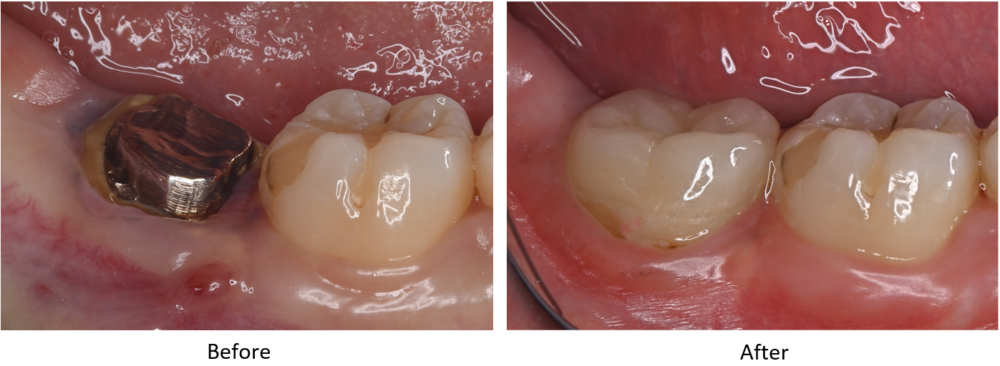

症例2

| 患者様データ | 40代 男性 |

| 来院時の主訴 | 「左下が痛くて噛めない。」 |

| 医院の診断 | 左下第一大臼歯歯根破折、慢性根尖性歯周炎 |

| 治療費 | 総額:275,000円(税抜) 【内訳】 歯牙移植150,000円、ファイバーポストコア20,000円、セラミック治療85,000円、歯頸部ダイレクトボンディング10,000円×2 |

| リスクと副作用 | ①根管治療歯は長期的には破折するリスク ②長期的なメインテナンスが必要 ③歯根の外部吸収 |

抜歯が必要になった際に余っている親知らずがあれば移植歯として利用することができます。 術前に撮影したCT画像から3Dプリンターを用いて親知らずのレプリカを作製することで、親知らずが乾燥することを防ぎ、成功率が上がるよう努力しています。 |